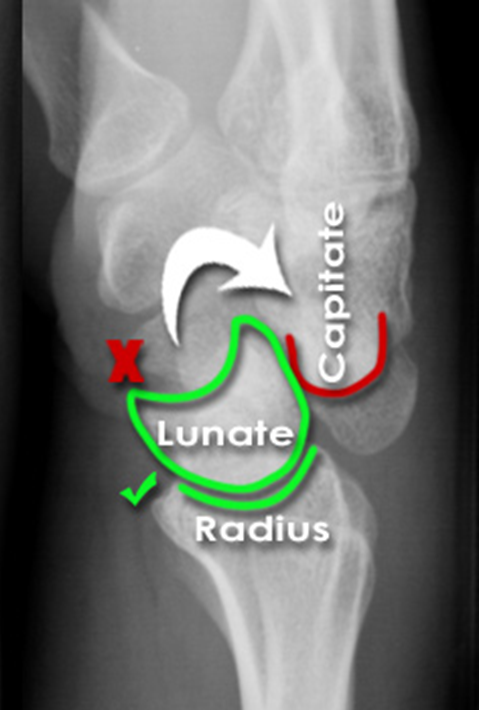

Peri-lunate dislocation

The image shows dorsal dislocation of the capitate which should be congruous with the cup of the lunate